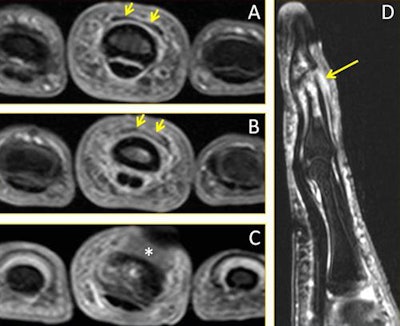

A 28-year-old male volleyball player with a finger injury. Consecutive axial fat-suppressed T2-weighted MR images of the third finger: (A) Proximally, there is normal appearance of the distal extensor tendon (short arrows); (B) Distally to A, the distal extensor tendon is thickened with increased signal intensity (arrows); (C) More distally to B, the distal extensor tendon is no longer depicted (*), consistent with a complete distal rupture. (D) Sagittal fat-suppressed T2-weighted MR image of the third finger depicts the complete rupture of the distal extensor tendon (arrow). The associated impaction fracture and bony contusions about the distal interphalangeal joint also are seen. Image courtesy of Dr. Daichi Hayashi, PhD.Recent studies show the incidence of volleyball-related injuries is between 1.7 and 3.0 injuries per 1,000 hours of play, and many injuries occur due to repetitive jumping and hitting the ball overhead, he pointed out. Most injuries occur among players in front-line positions, which is where jumping and landing occur most often. Most injuries involve the lower extremities, and match injuries are more frequent than training injuries.

- Hand/finger injuries -- Direct contact of the hands and fingers with the volleyball is the main cause of these injuries, which may occur while setting, spiking, serving, or blocking, and many injuries are acute. The majority are ligament and capsule sprains. Receivers may be at risk of tendinopathy and superficial neuropathy, especially at the first dorsal extensor compartment of the hand/wrist. De Quervain's tenosynovitis can occur due to repeated microtraumas at the dorsal and radial aspect of wrist, which is employed in the volleyball receiving position. Mallet finger injuries can occur when an extended finger is struck on the tip by the ball, and it is due to a flexion force applied on the tip of the finger, while the distal interphalangeal joint is fully extended.